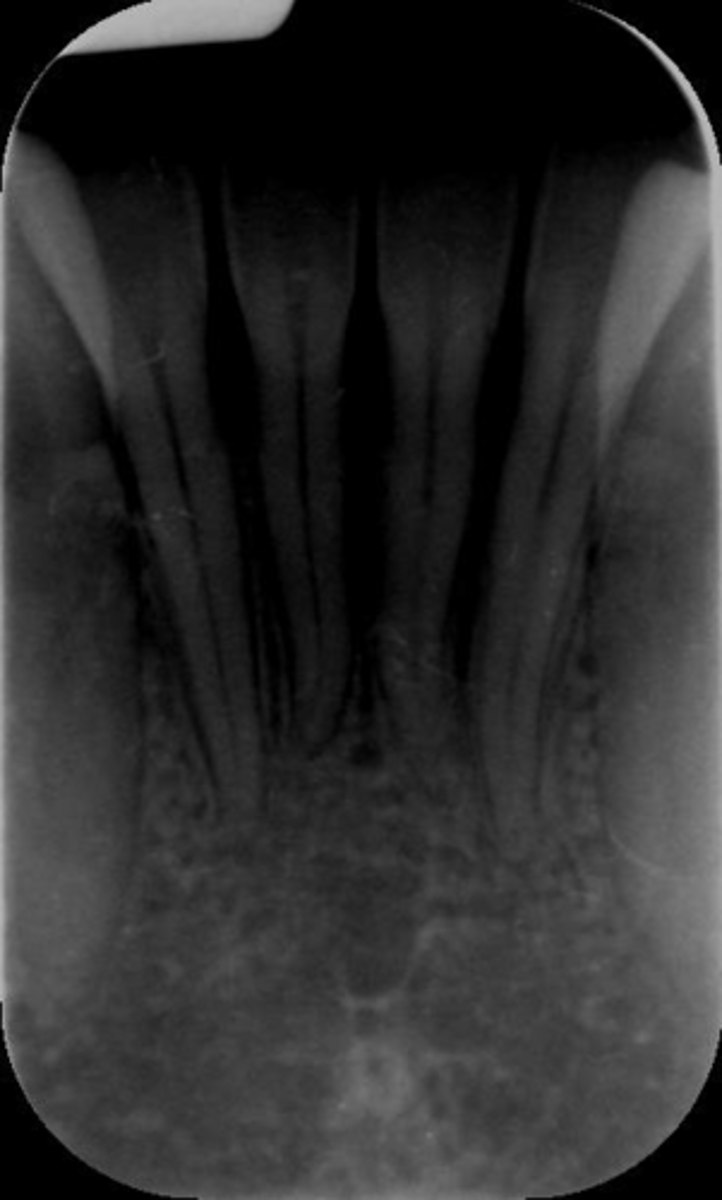

What is this error?

Remove glasses

Wrong film direction, backwards, positive angulation, wrong film size, no open contacts